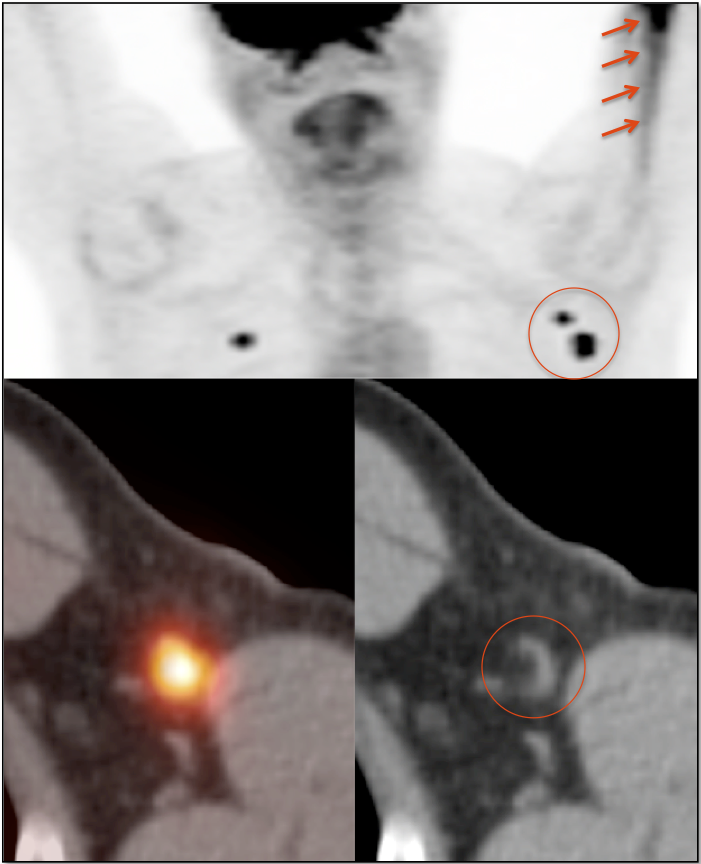

- Elastofibroma Dorsi